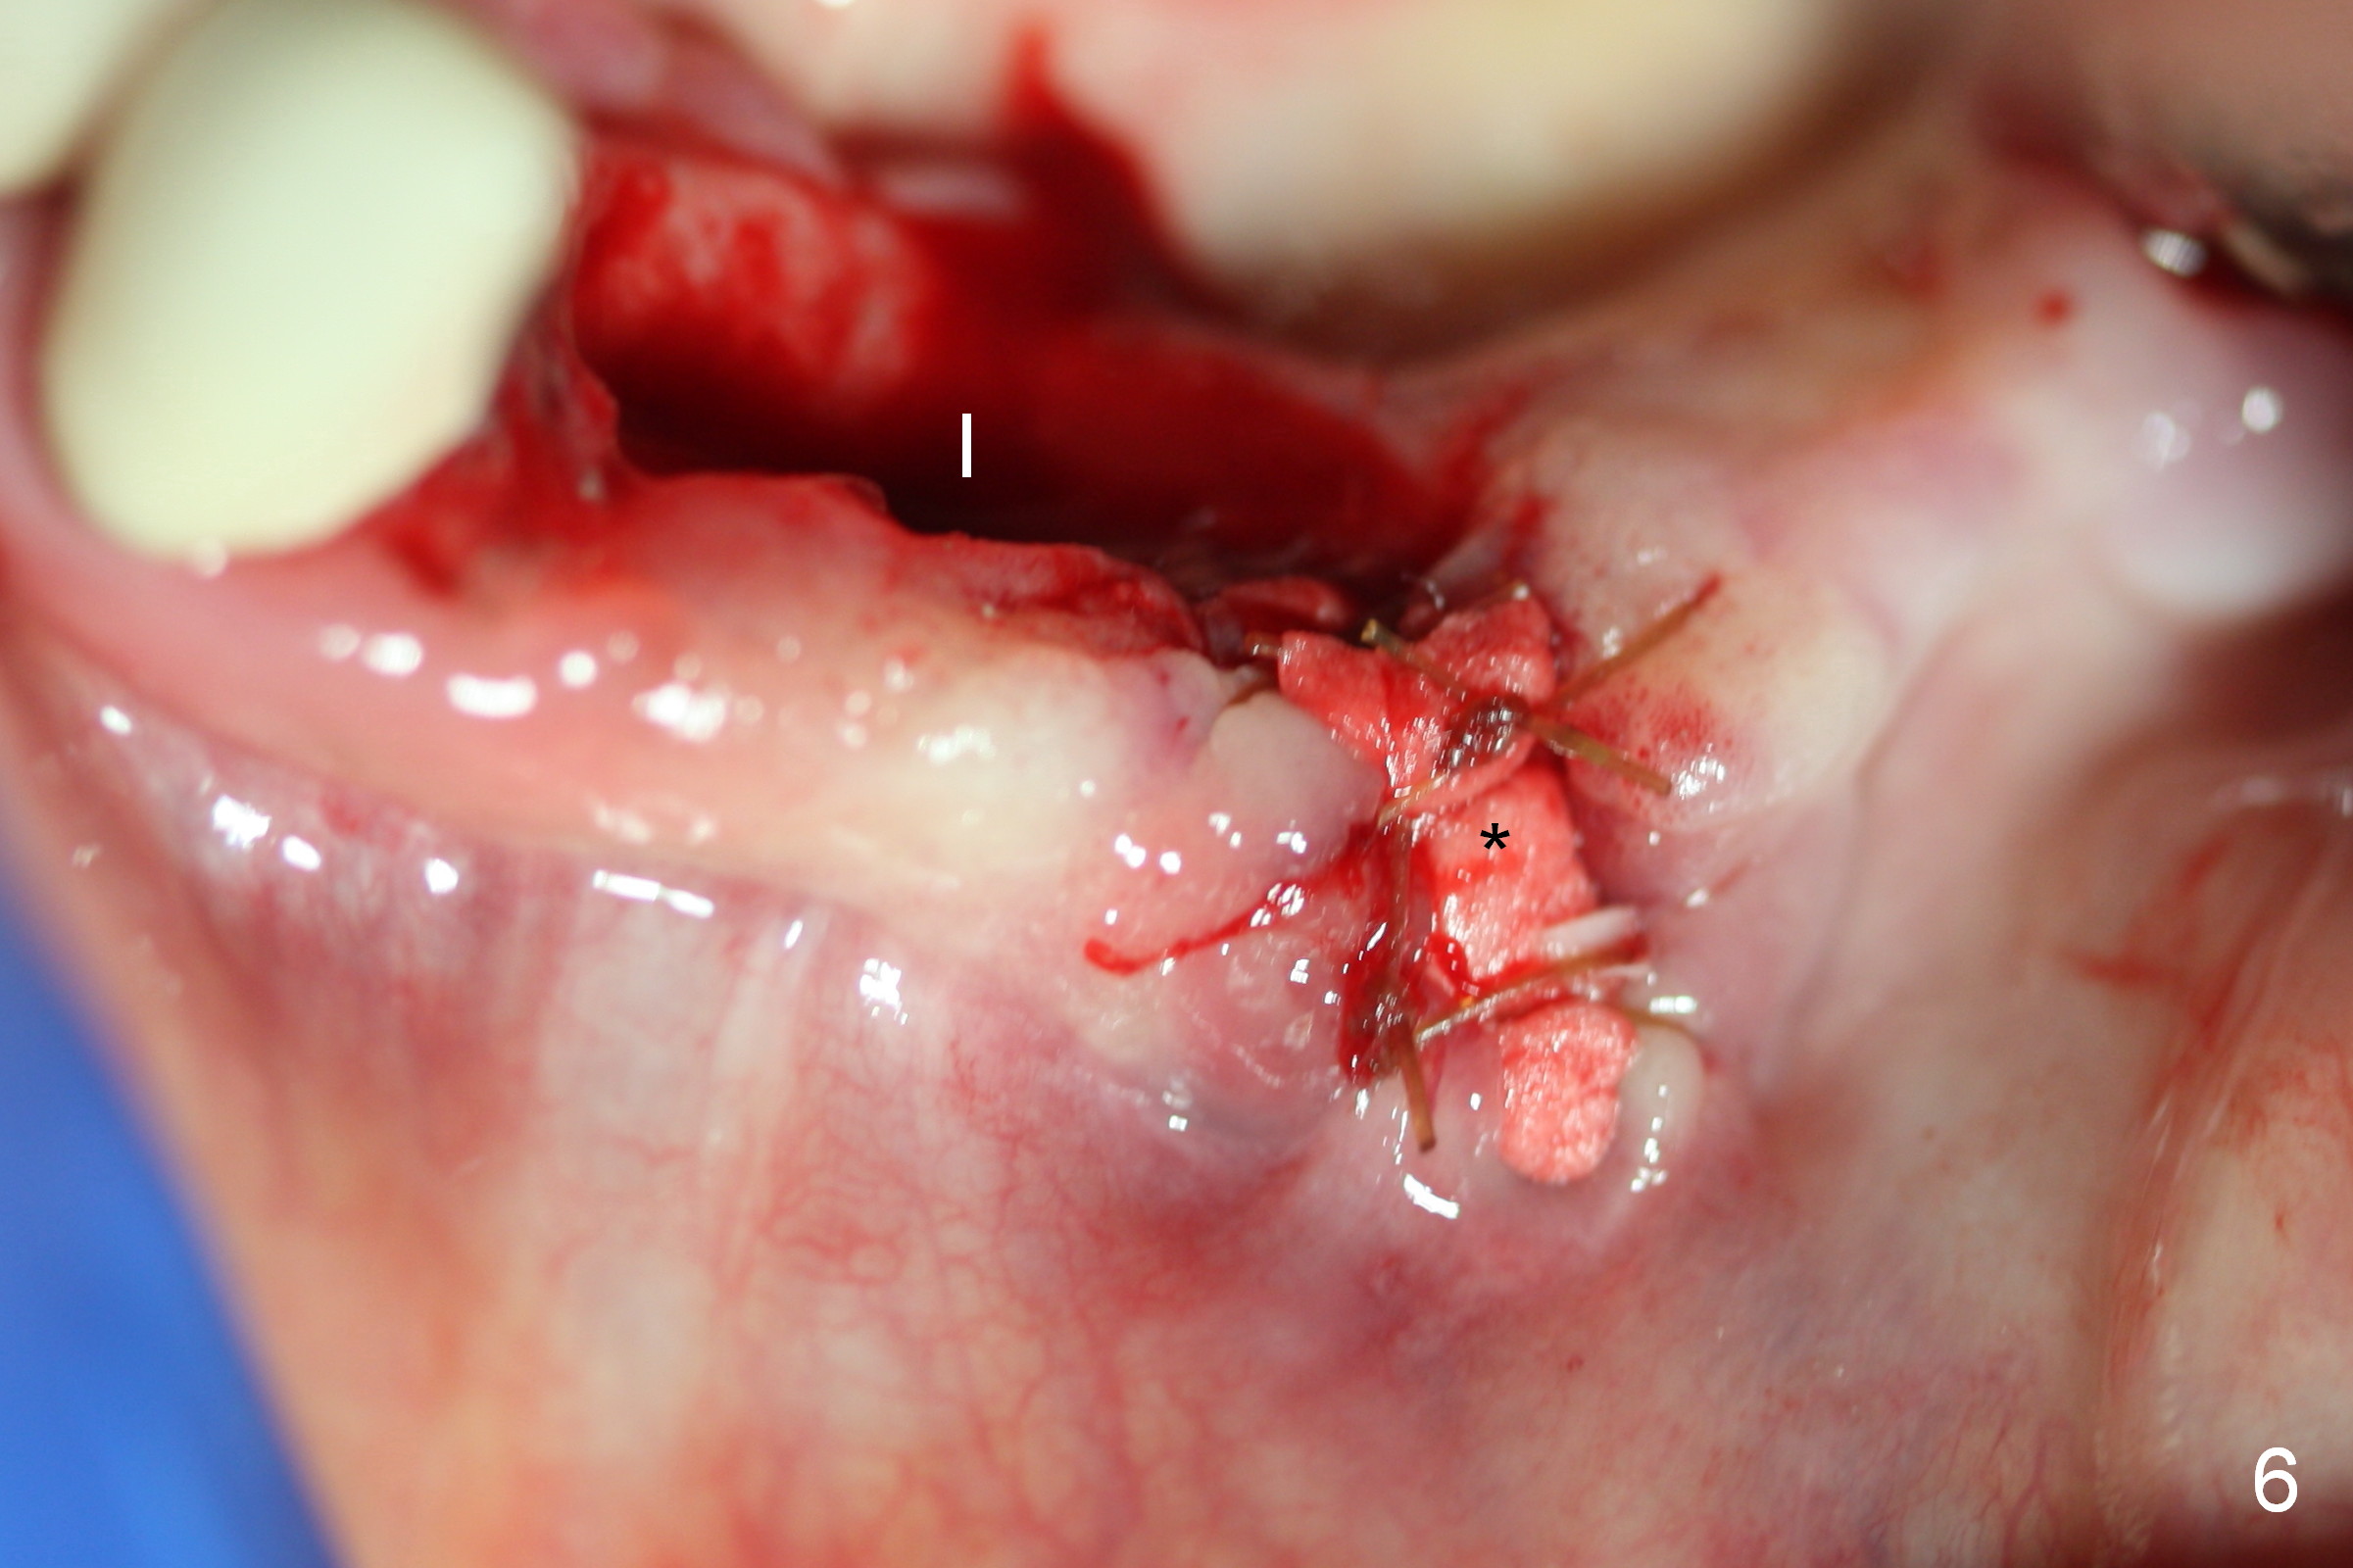

A 72-year-old woman has severe pain associated with one of three abutments of a long-spanned bridge (Fig.1,2: #22). The lingual calculus is extremely large (Fig.3 C). When the bridge is sectioned between #26 and 27, the tooth #22 is easily separated from the socket (Fig.4). In fact, the large supragingival calculus causes hemorrhagic indentation in the lingual vestibule (Fig.5,6: I). Due to finance, socket preservation is done at #22 with 6-month collagen membrane buccally and .5-1.5 mm allograft and collagen plug (Fig.6 *).